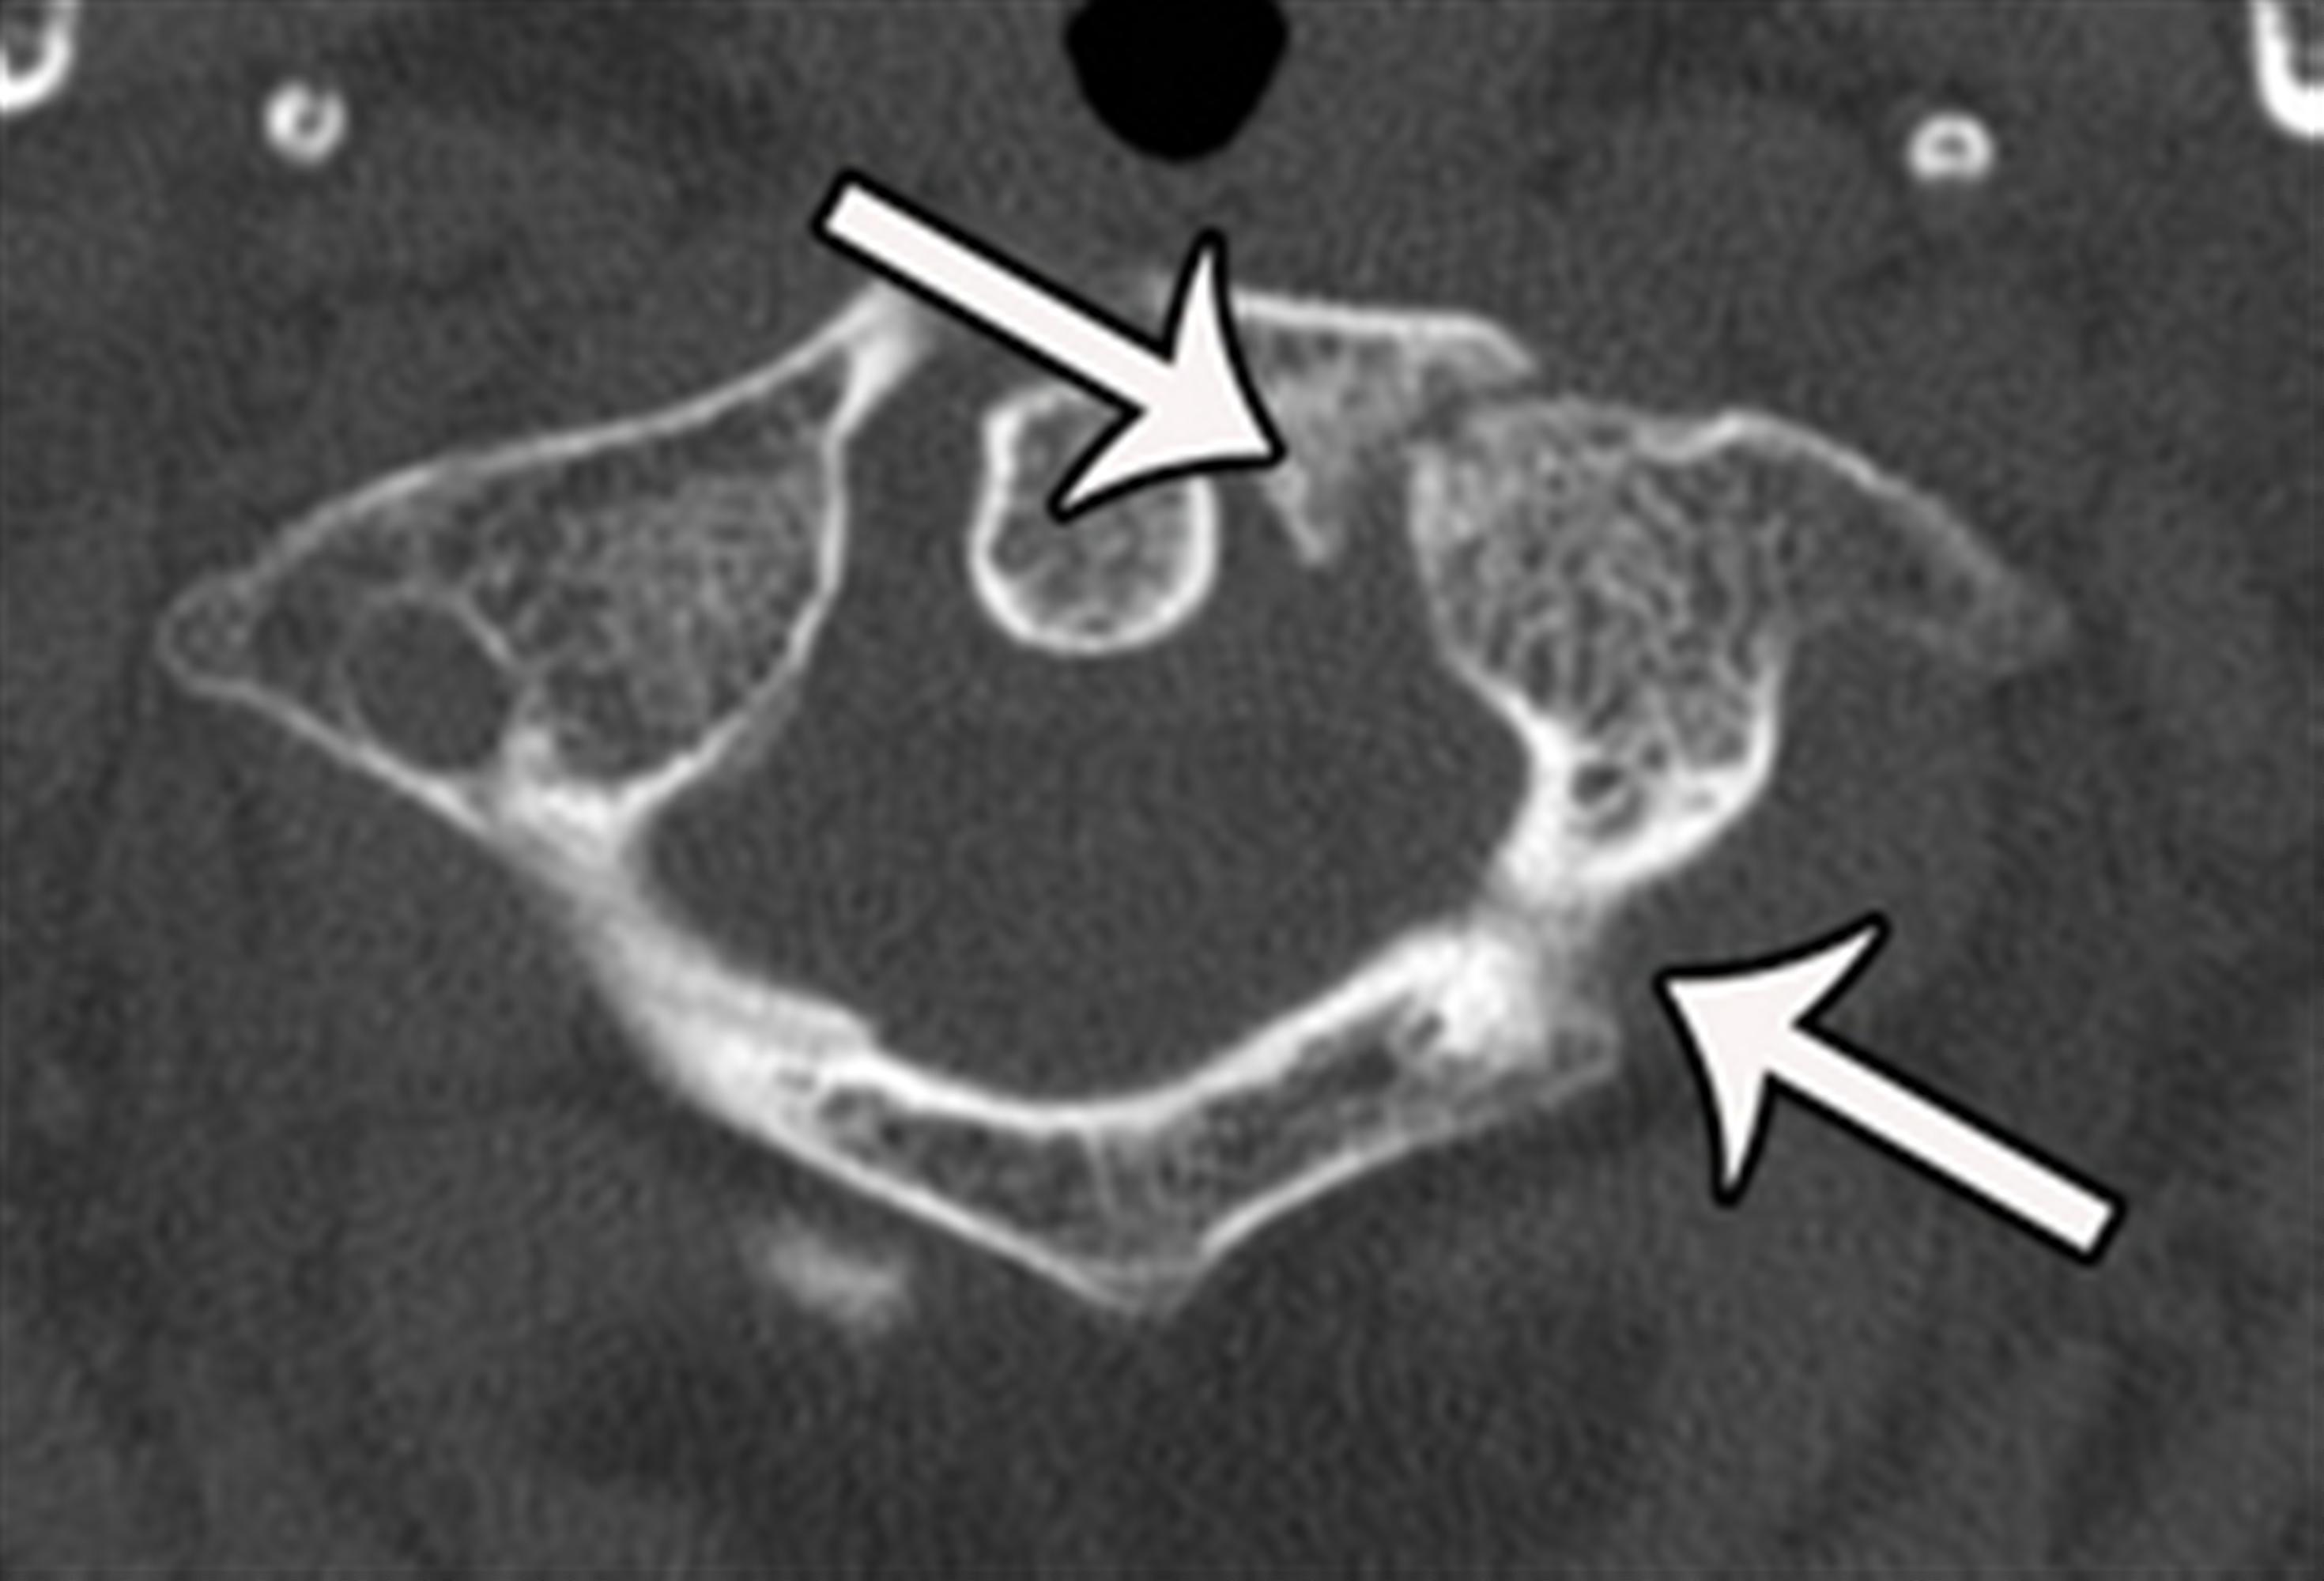

From www.nassopenaccess.org

Isolated Thoracic and Lumbar Transverse Process Fractures Do They Need Treatment Transverse Process Fracture Your broken bones need to heal back together. Defined as those involving the transverse process only, without extension into the pedicle, lamina, or facet complex. How are transverse fractures treated? To review the literature on isolated transverse process fractures (itpfs) and provide evidence for the current practice of. A transverse process fracture is typically the result. Transverse fractures are a. Treatment Transverse Process Fracture.

Isolated thoracic and lumbar transverse process fractures Do they need Treatment Transverse Process Fracture Transverse fractures are a specific type of bone breakage that occurs perpendicular to the long axis of the bone. Your broken bones need to heal back together. Here, i will detail the causes, symptoms, how this fracture is diagnosed and finally, how i would treat this type of fracture. Defined as those involving the transverse process only, without extension into. Treatment Transverse Process Fracture.